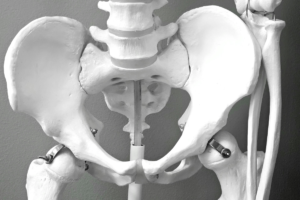

骨盤を見る理由

骨盤は、

立つ・座る・歩くといった動作の中心です。

ここに偏りが出ると、

腰や肩が代わりに頑張ることになります。

骨盤矯正は、無理に動かすのではなく、

負担が集中しない位置を探す作業です。